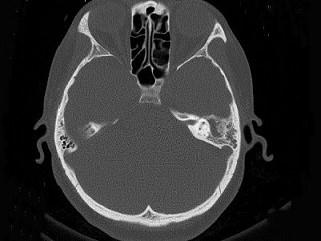

问题 女,34岁,左耳鸣,听力下降两个月,PE:左外耳道有脓性分泌物,鼓膜充血水肿,左中耳腔内软组织影,CT检查如图,最可能诊断为 ( )

选项 A、肉芽肿形成 B、中耳结核 C、中耳癌 D、胆脂瘤 E、乳突癌

答案 A